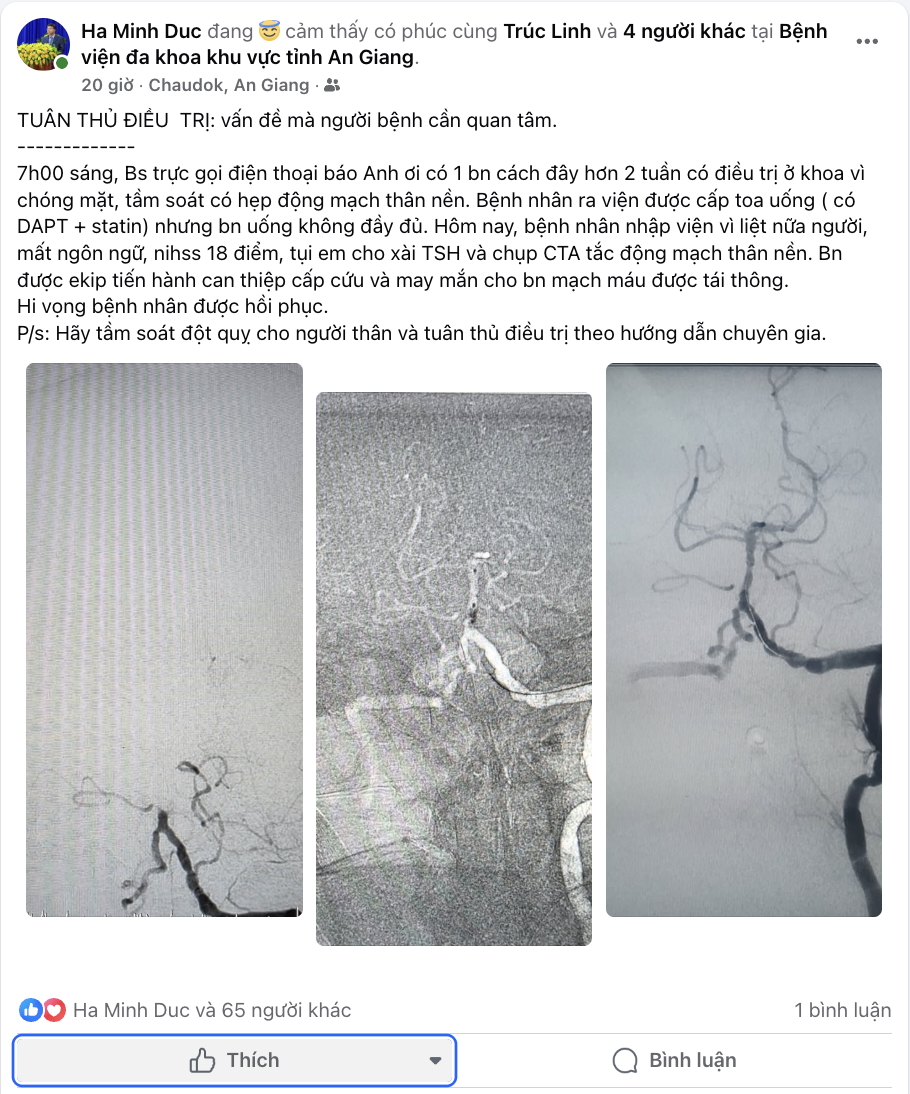

Ngay lập tức, ekip cấp cứu đã chỉ định tiêu sợi huyết và chụp CTA. Kết quả cho thấy tắc động mạch thân nền. Đây là một tình huống tối cấp, nguy cơ tử vong rất cao nếu không được xử lý kịp thời. May mắn, sau can thiệp cấp cứu, mạch máu được tái thông.